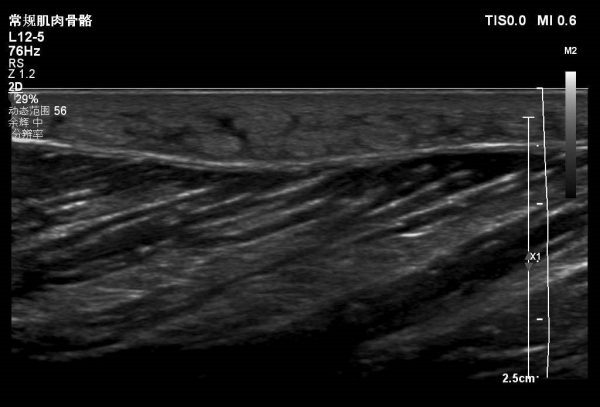

大腿包块—病例

患者大腿远端浅表可见一包块隆起,自述半月前出现红肿,目前未见明显红肿,触摸感觉微痛。

根据病情考虑可能蚊虫叮咬水肿。大家考虑是什么?有没有专家给看看,是什么?谢谢。